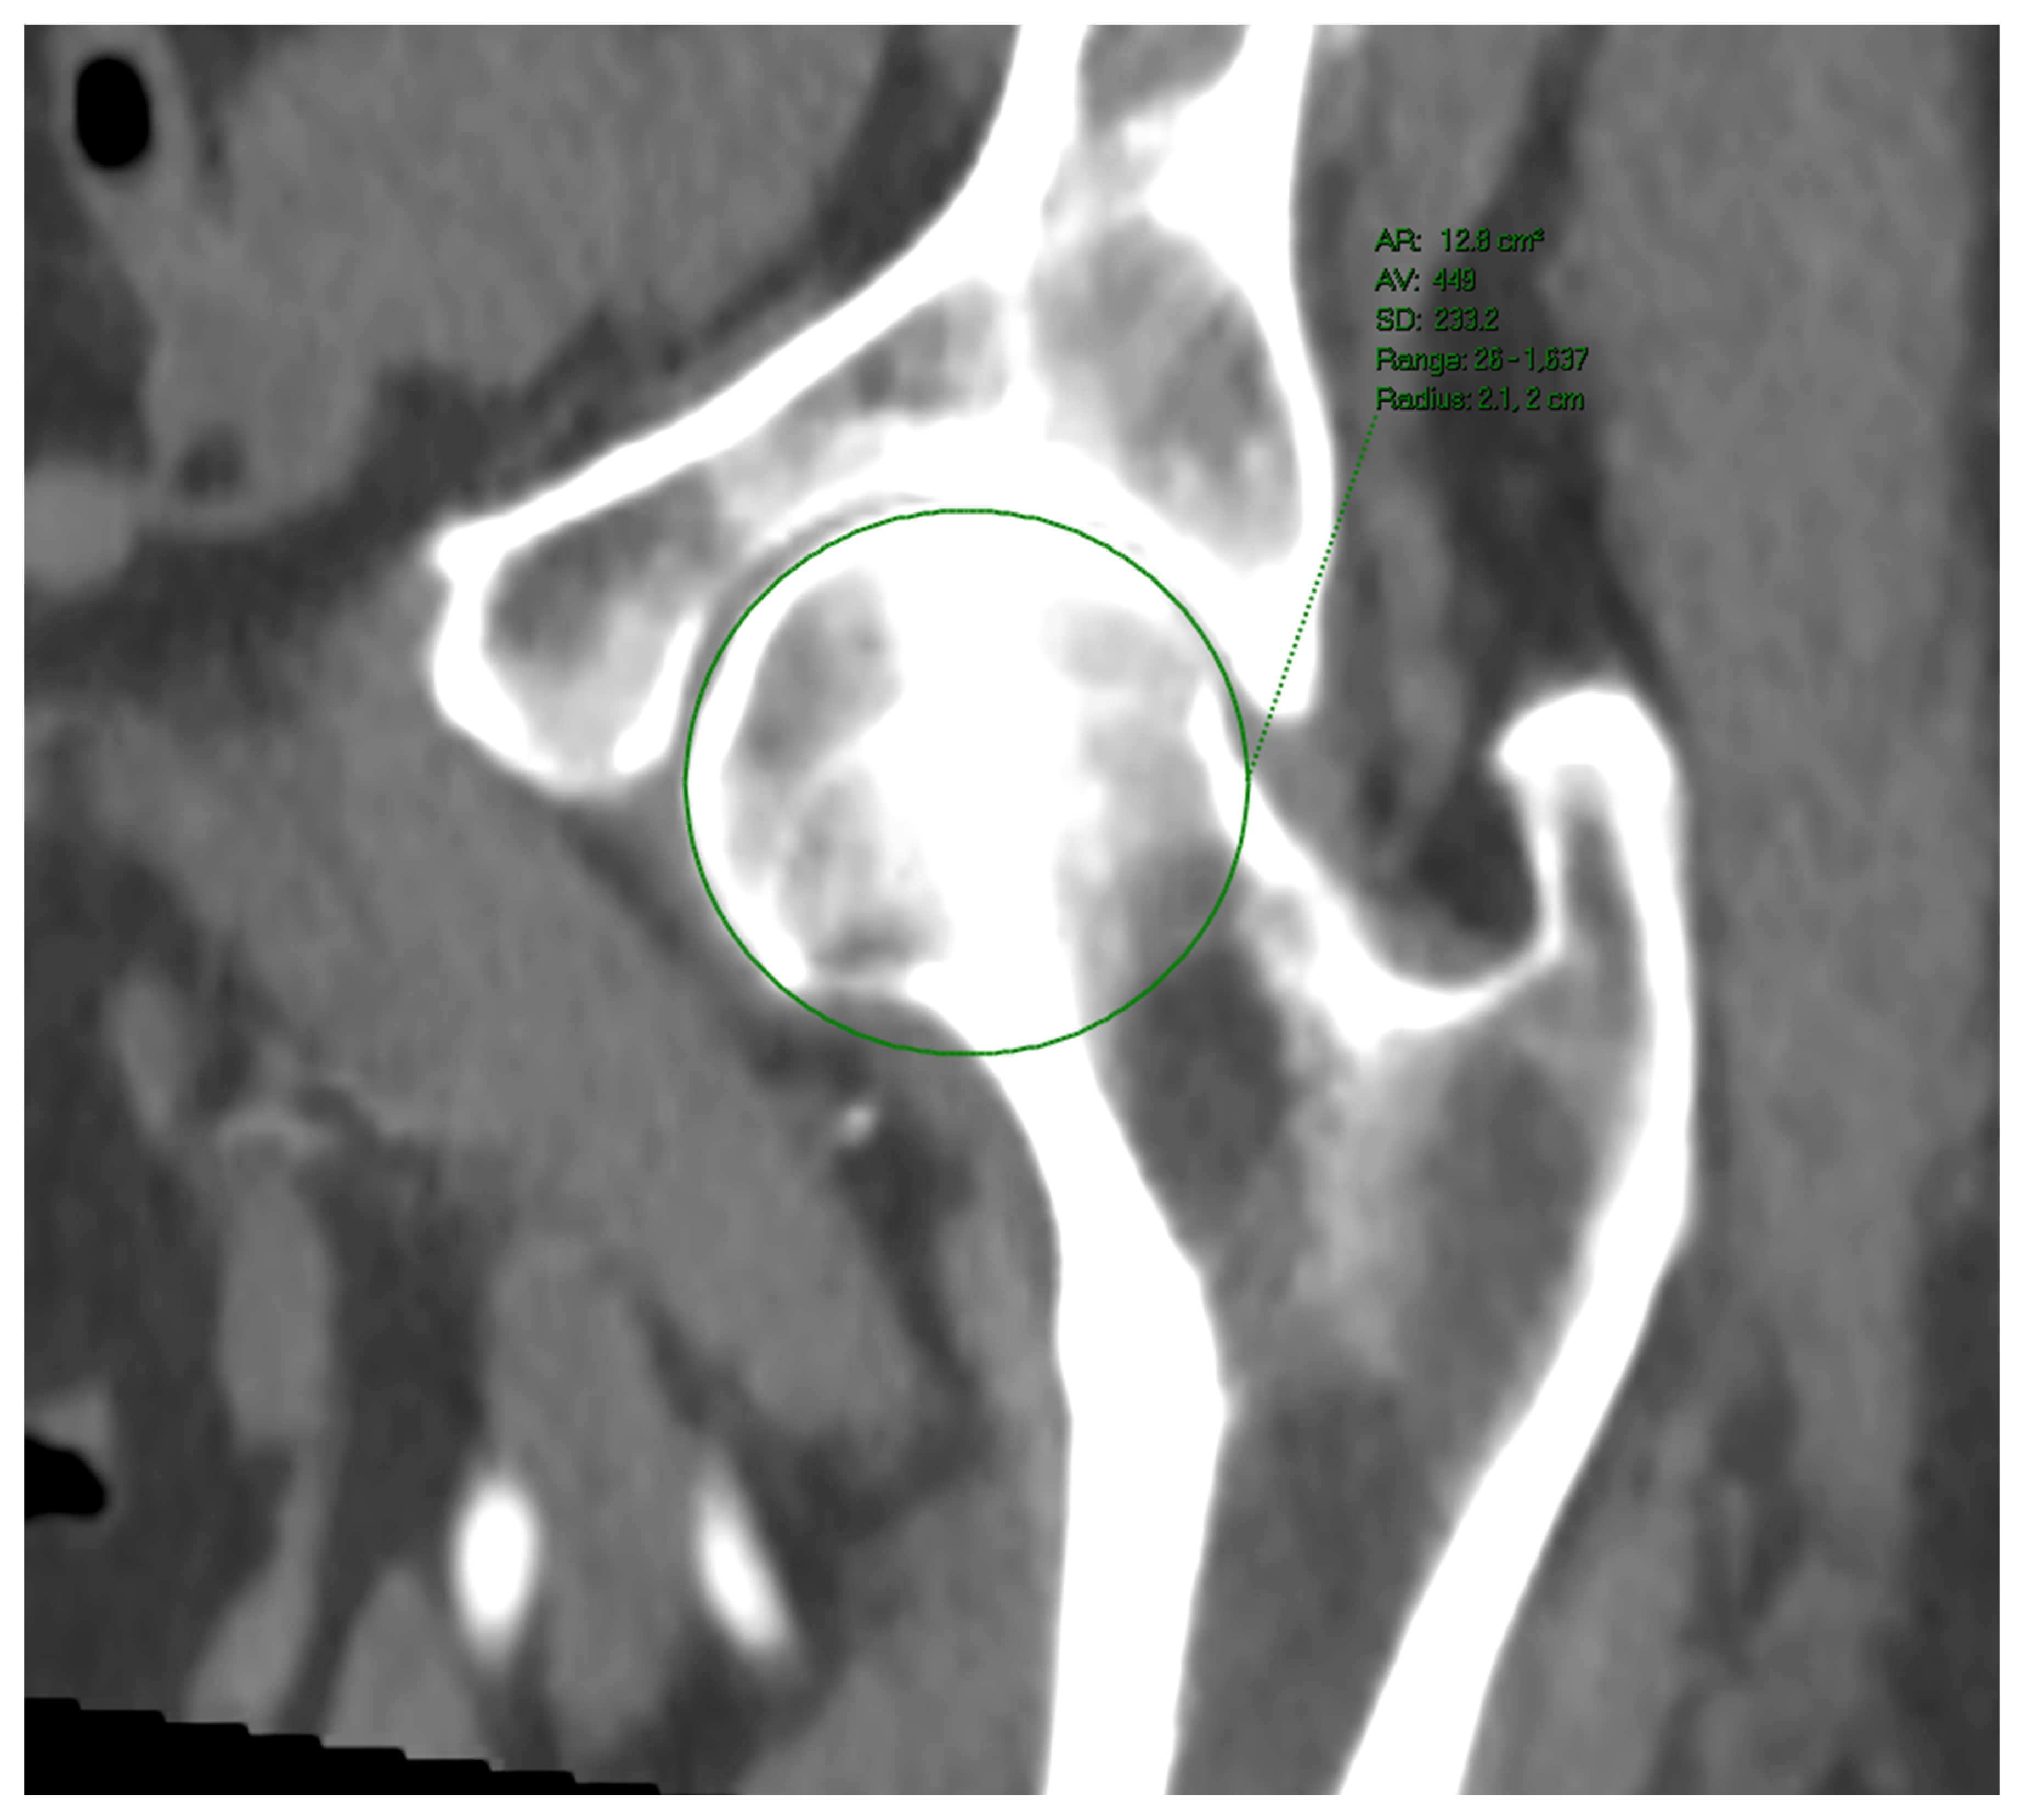

Femoral head diameters and perimeters were measured upon a multiplanar reconstruction of the relevant anatomical region. The measurements were performed in at least two planes, all crossing each other in the center of the femoral head. The diameter measured in a plane lying in parallel with the acetabular rim plane was chosen (Figure 3). Patients with femoral joint replacement (even unilateral) or any deformation of the femoral head and acetabulum were excluded from the study. Patients within whom an even semicircular femoral head surface could be demonstrated (due to osteophytes or synovial changes) were excluded, too.

Figure 3.

Femoral head perimeter measured upon MSCT.